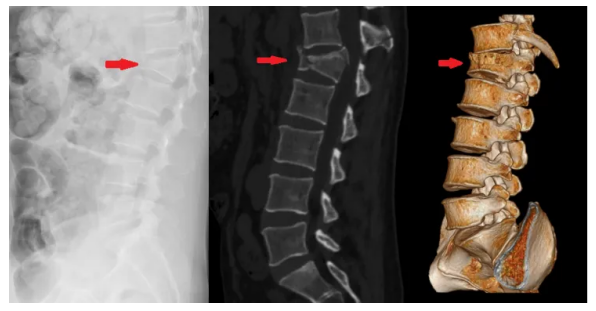

左图为X线片,中图为三维CT矢状面重组,右图为三维CT容积重建。

X线片可见腰1椎体压缩变扁,但是难以看到内部骨折线的走向和断裂部位情况以及附件骨折。矢状面重组和容积成像,清晰显示骨折线走向、骨性椎管以及附件骨折,为手术方案的制定提供重要信息。